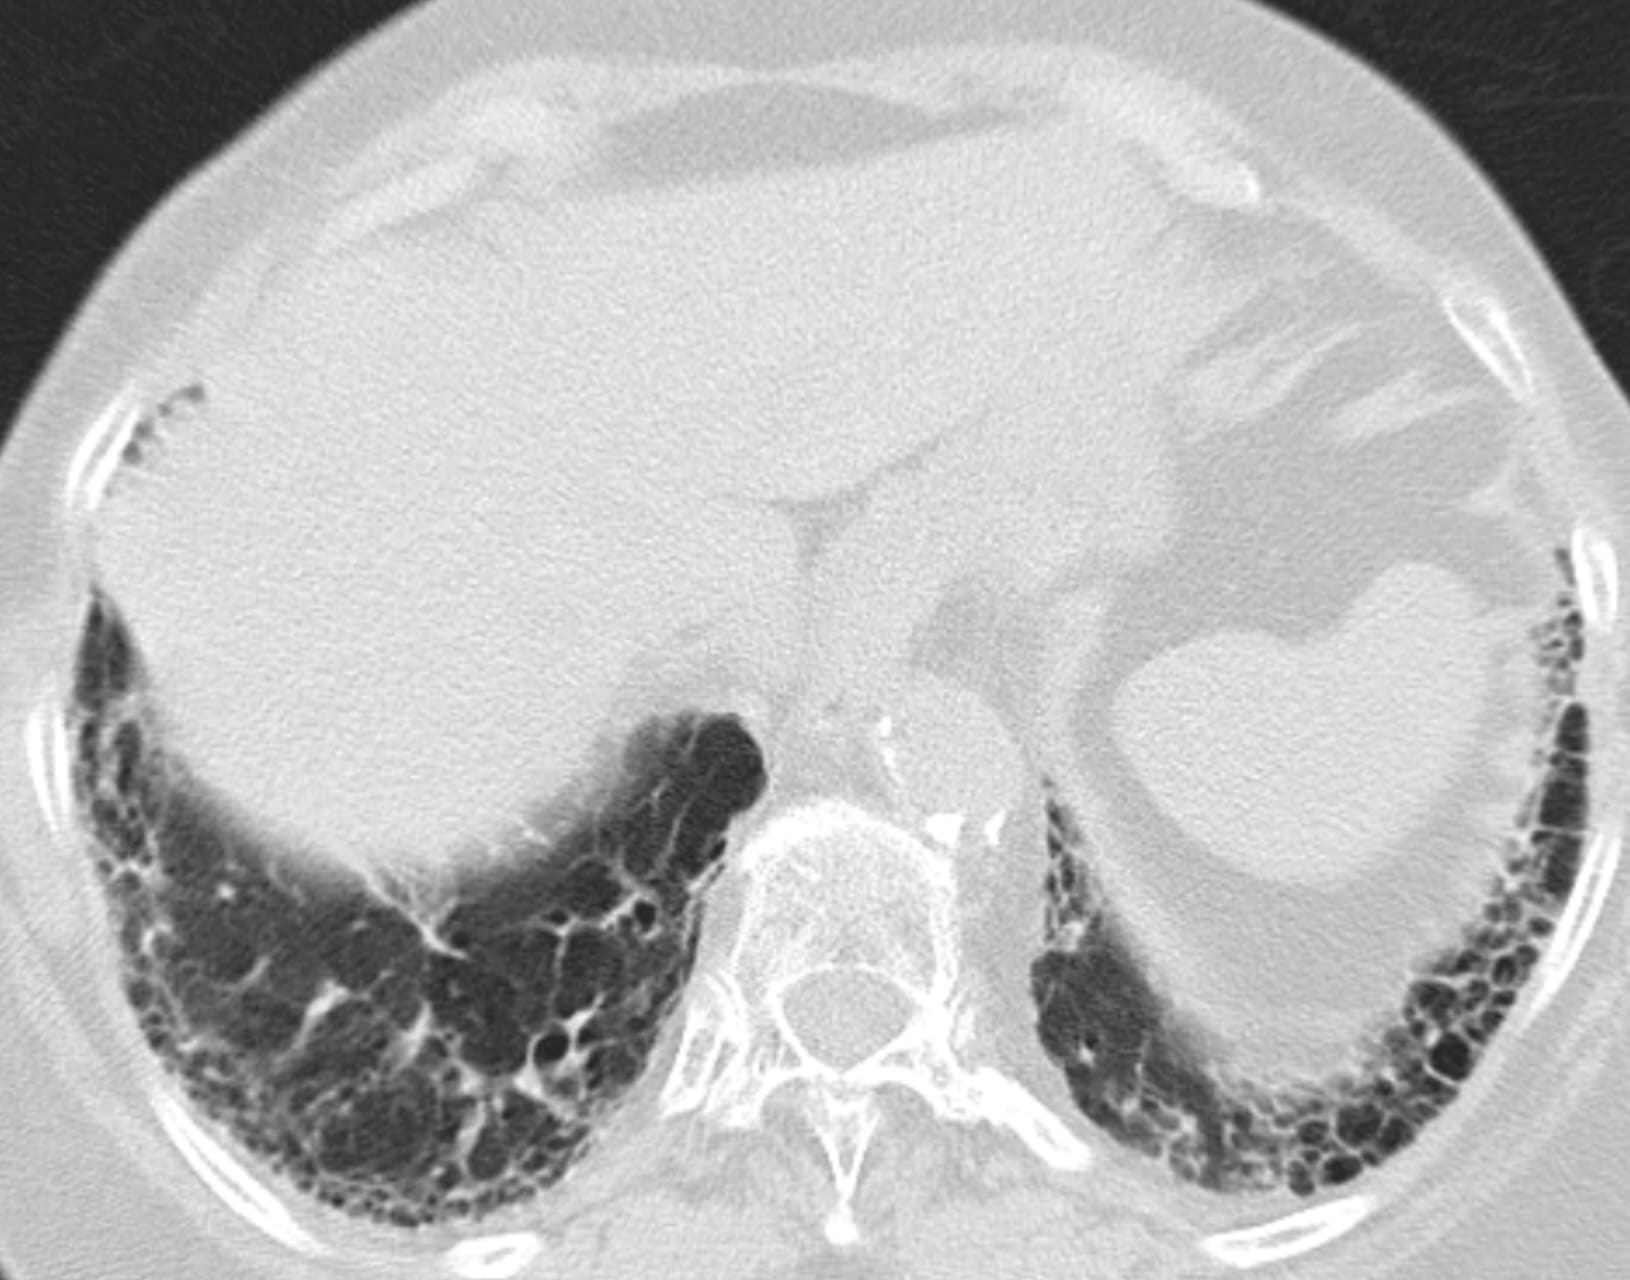

- Usual Interstitial Pneumonia